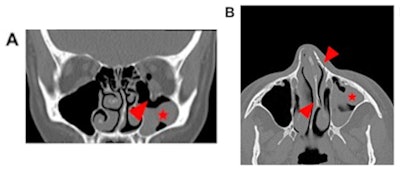

Most conditions related to intimate partner violence are fractures in the face (48.3%), fingers (9.9%), or upper trunk (9.8%), and it can be easy to interpret them as routine trauma, according to the authors. That's why radiologists should thoroughly review the medical history of cases that are suspicious for domestic abuse, discuss these cases with the referring physician, and conduct a private conversation with the patient, educating them on available resources for victims, the authors wrote.